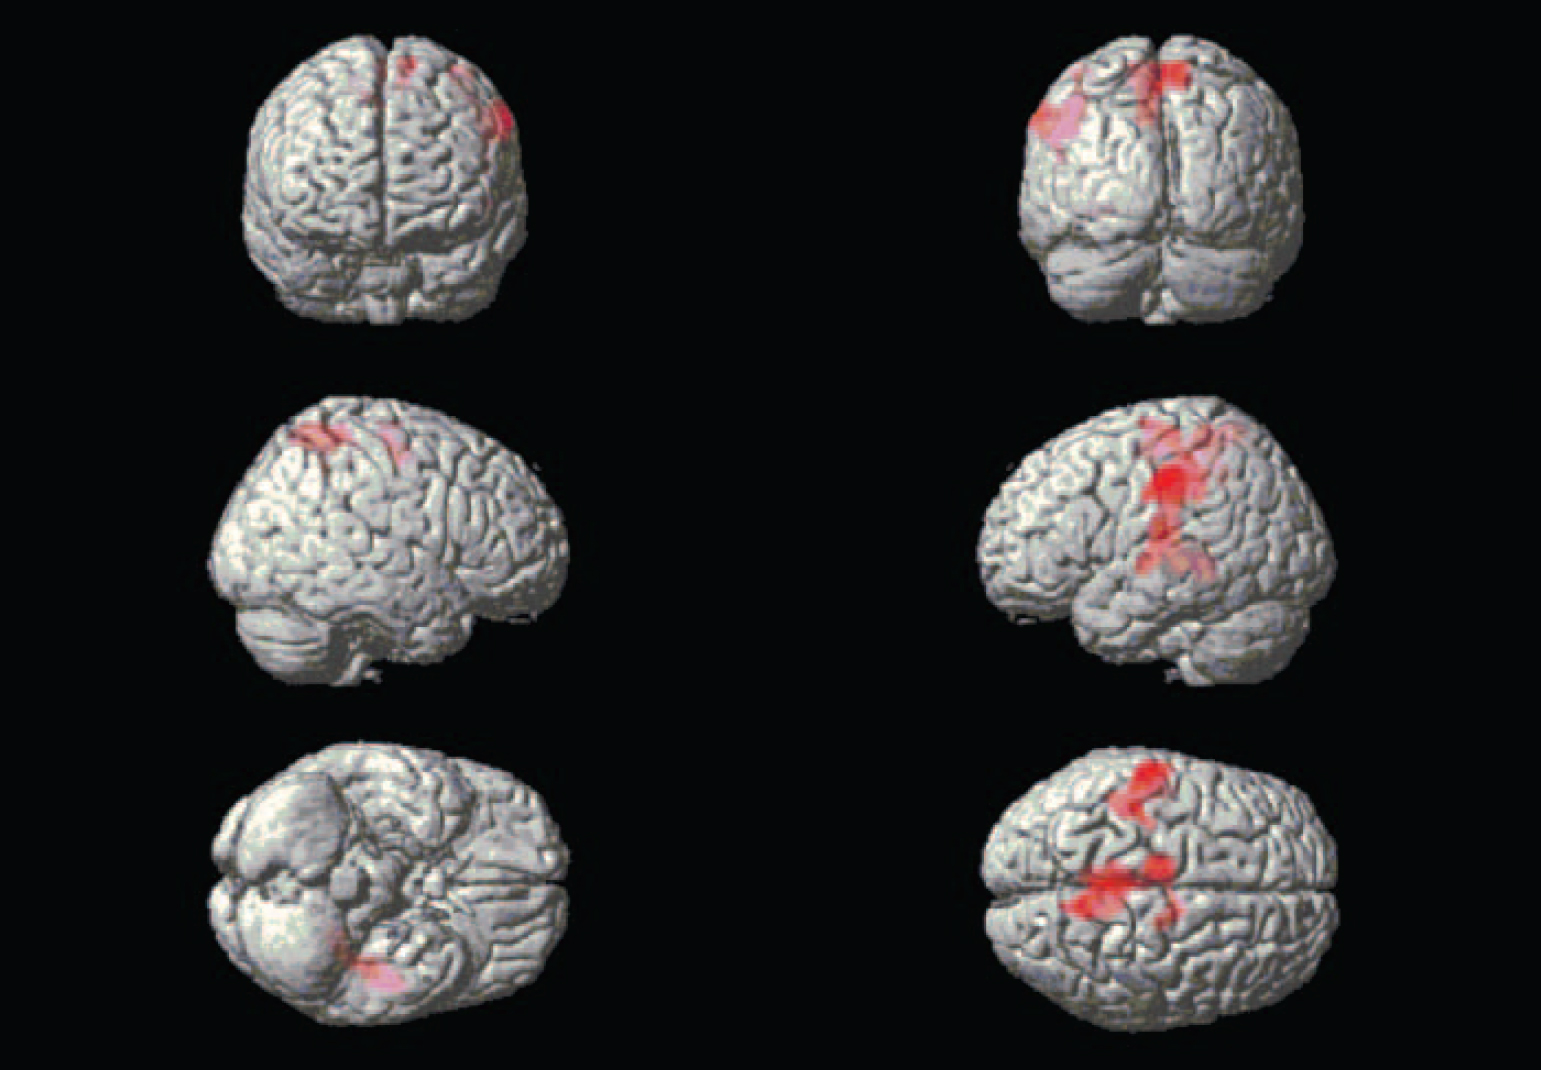

Whole-brain exploration. Differences in large cluster activations emerged between the groups in both directions. During the combined emotional films, the alexithymia group had lower activation in large parts of the occipital and posterior lobes in comparison with the non-alexithymia group, forming two clusters, one for each hemisphere (Fig. 1). The three peak activations for each cluster are presented in Table 1. There were also two large higher-activation clusters for the alexithymia group, located mainly in the middle and left-side parts of the brain (Fig. 2). The three peak activations for each cluster are presented in Table 2.

Fig. 1 Brain areas exhibiting less activation in the participants with alexithymia.

Fig. 2 Brain areas exhibiting more activation in the participants with alexithymia.